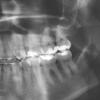

sem2005 Опубликовано 16 декабря, 2012 Автор Поделиться Опубликовано 16 декабря, 2012 Ну вот, наконец-то получилось сделать прицельный снимок 26. По этому снимку можно что-то сказать? Ссылка на комментарий

Scrabble Опубликовано 18 декабря, 2012 Поделиться Опубликовано 18 декабря, 2012 Я за семёрку-там кариес на контакте и пломба огромная. Для уверенности можно холодовую пробу сделать в кресле. Ссылка на комментарий

sem2005 Опубликовано 21 декабря, 2012 Автор Поделиться Опубликовано 21 декабря, 2012 Там пломбы такие большие на 6ке и 7ке, потому что еще год назад искали кариес на контакте, но так и не нашли - было только потемнение эмали на контакте http://www.kolobok.us/smiles/icq/pardon.gif Ссылка на комментарий

Scrabble Опубликовано 28 декабря, 2012 Поделиться Опубликовано 28 декабря, 2012 Ещё раз повторю: у Вашей жены пульпит. По снимкам мы можем только предположить, в каком квадранте, потому что периапикальных изменений при пульпите нет. Чтобы выяснить, какой зуб точно, необходимо клиническое исследование(то есть в кресле стоматолога) Потом делать эндо. Тогда всё пройдёт. Надо к врачу идти, а не страдать от боли около монитора... Ссылка на комментарий